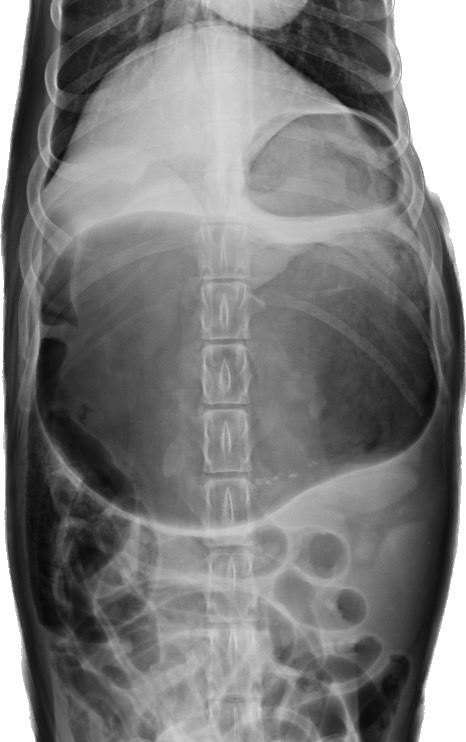

看到如此的症狀,答案也呼之欲出了,在X光下,小巴的胃非常擴張,且幽門部往前背側、左側位移,診斷為“胃擴張扭轉“

圖為腹腔X光